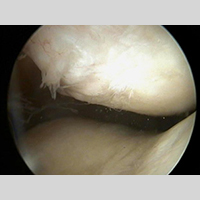

Ortopedi (ARTROSKOPİ)

Artroskopi Seti (Teleskop-Kılıf- Forsepsler)